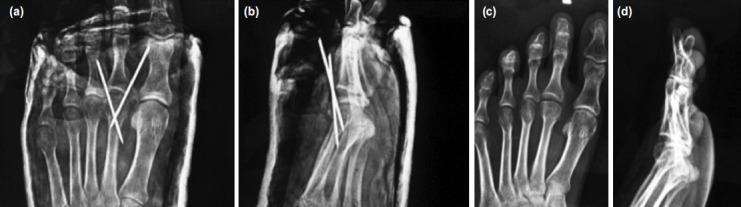

Twenty patients with Freiburg's infraction were admitted at our hospital over a period of six years. Patients with a normal plantar contour of the metatarsal head were included. All patients underwent a dorsal closing wedge osteotomy of the metatarsal.

The mean Leeds Movement Performance Index (LMPI) score was 84 (range 70-86). The mean metatarsal shortening was 2mm. the passive flexion restriction was 16° and extension restriction was 10°. Also, a strong negative correlation was found between Smillie classification and American Orthopaedic Foot and Ankle Score (AOFAS) final score (r's = -0.85, P < .001).

六年间,我院收治了20例弗赖贝格骨折患者。纳入跖骨头足底轮廓正常的患者。所有患者均接受了跖骨背侧闭合楔形截骨术。

利兹运动表现指数(LMPI)平均评分为84分(范围70 - 86分)。跖骨平均缩短2mm。被动屈曲受限16°,伸展受限10°。此外,斯米利分类与美国矫形足踝协会评分(AOFAS)最终评分之间存在强负相关(r's = -0.85,P <.001)。